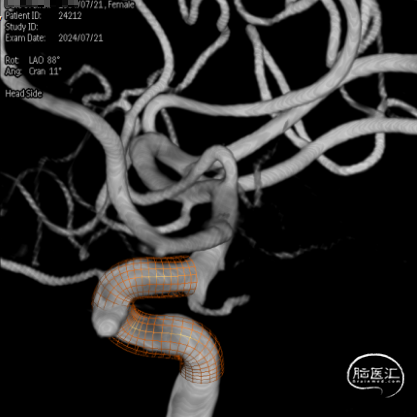

术前在3D状态下测量及进行支架模拟

通桥麒麟™血流导向密网支架 5.0*25mm

沿着XT-27微导管送入通桥麒麟™血流导向密网支架 5.0*25mm,通过造影对好位置后,缓慢回撤微导管释放支架,释放过程中随血管形态进行适度推拉。